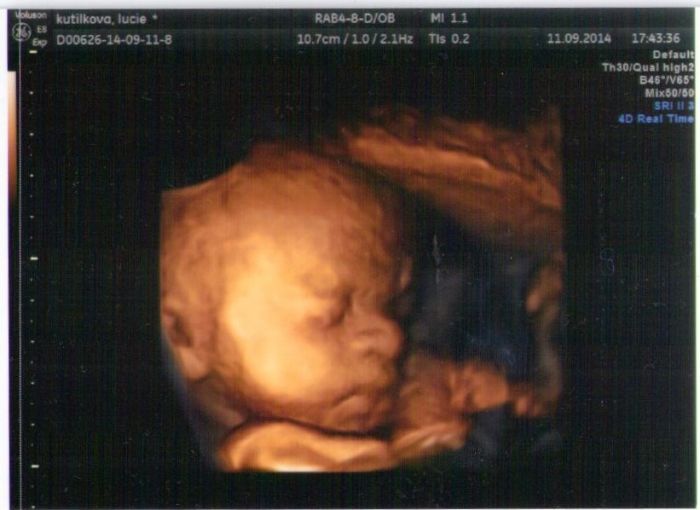

no já se nemžuu dočkat až malá bude venku už je to celkem těžkej náklad:D a příjdu si už jako tank:D ....jinak holky pujdete na 3D ultrazvuk? já tam byla a je to bezvadný vidět ješla malou před porodem ... uplně mě to dojalo :-)